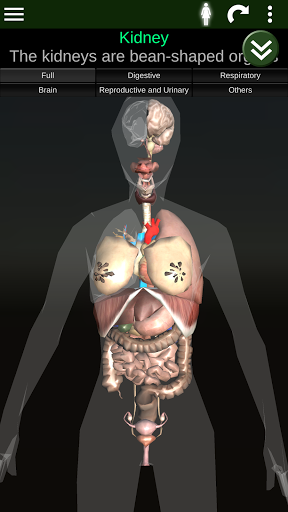

Internal Organs in 3D Anatomy لـ Vodafone Smart N9 Lite

(الأجهزة الداخلية في)

Internal Organs 3D Anatomy 3.4